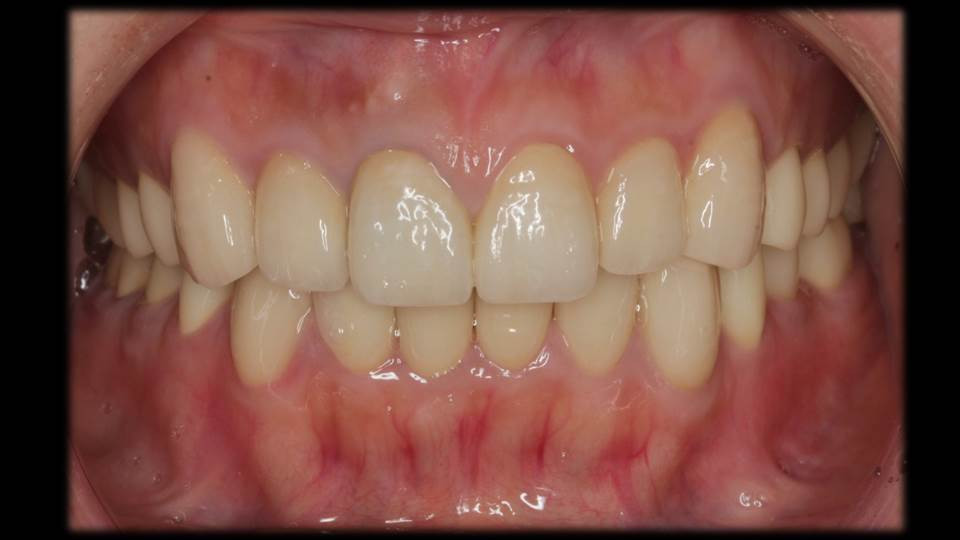

治療後のお口の中の様子

お口の中のバランスがとれています。

全体的にセラミックスの被せ物で治療を行なって1年経過した時の写真です。歯茎の状態も良く,歯並び・咬み合わせ共に安定しています。定期検診・慎重な経過観察が重要です。